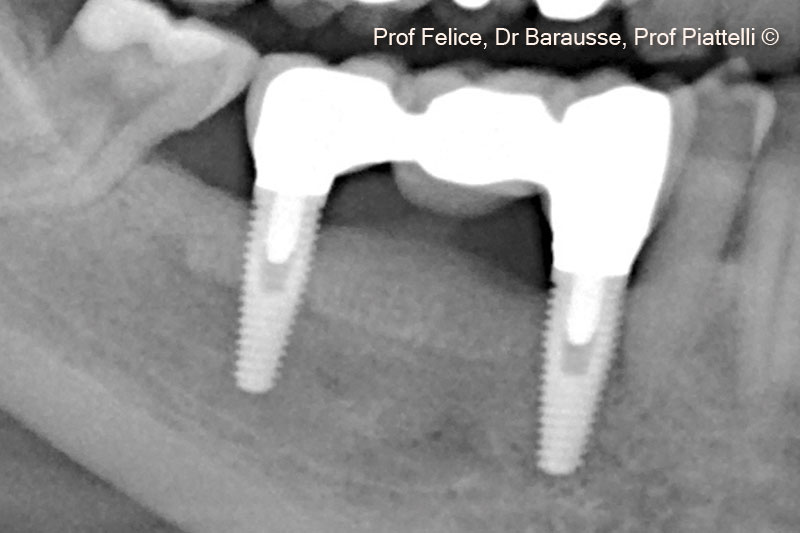

Một bệnh nhân nữ (70 tuổi) có biểu hiện teo xương hàm dưới bên phải phía sau.

Evolution